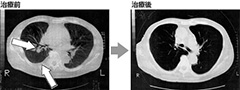

画像引用元:日比谷内幸町クリニックHP(http://www.hu-clinic.com/case/case_22.html) 高齢男性―【大腸がん切除後肺に転移】大腸がん切除から9年、肺と骨に転移。腎臓にトラブルがあり手術不可能、抗がん剤を勧められるも拒否。免疫療法開始2年でがんが消失。